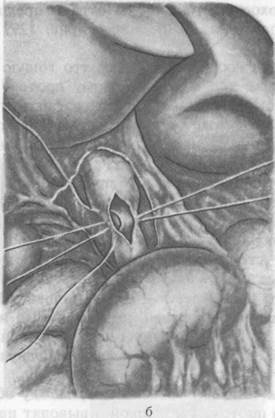

Анатомия и особенности Гартманова кармана желчного пузыря